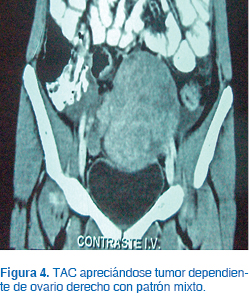

Se realizó USG, encontrándose un tumor con ecogenicidad mixta (Figura 3). La TAC mostró un tumor dependiente de ovario derecho con dimensiones de 6 x 9 x 9 cm de diámetro, con patrón mixto (Figura 4). Se realizó la determinación de alfa fetoproteína, con resultado de 2 μg/L; la fracción β de la gonadotrofina coriónica fue de 1 mUI/mL; la hormona luteinizante (LH), de 6 mUI/mL; la hormona folículo estimulante (FSH) fue de 7.2 mUI/mL; prolactina, 15.9 ng/mL; estradiol, 2.6 pg/mL, y la 17-OH PROG (17-hidroxiprogesterona), de 0.5 ng/dL.